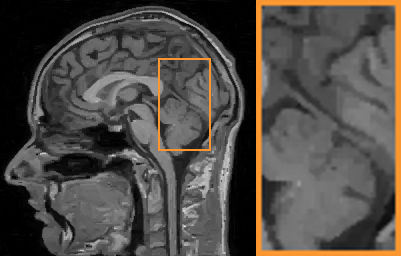

| Ground Truth (PSNR) | PANO (27.73) | FDLCP (26.84) | BM3D-MRI (26.27) | Ours (28.22) |

As shows in Fig. 1, at the first several iterations, the loss of is slightly larger than that of . Because the input is corrupted with severe artifacts, thus the role of data-driven module is significant at the first several steps. But as process goes on, repeated denoising operation in turn causes over-smoothing. While module can make up for it by incorporating model based knowledge. Though can improve the performance, it cannot ideally converge to a desired solution. The solid line indicates the superiority of Ours over other choices in both convergence rate and reconstruction accuracy. The execution time of , , and Ours is 4.4762s, 3.3240s, 6.2760s and 2.5225s, respectively. As expect, the proposed method provides a much faster reconstruction process. Thus we can verify that our framework has higher efficiency both in terms of theoretical convergence and practical execution time. The visualized results in Fig. 2 also verify that Ours has better performance than others.

First, we test on 25 T1-weighted MRI data using three different undersampling patterns with a fixed 10% sampling rate. Fig. 3 shows the quantitative results (PSNR). Our method performances best for all three cases and has stronger stability compared with the second best method on variance. As for the effect of sampling ratios variation, we use radial mask under 10%, 30% and 50% sampling rates with evaluation of RLNE and MSE. Fig. 4 shows that our method has the lowest reconstruction error for all sampling rates. For more intuitive comparison, we illustrate the reconstruction error in term of pixels in Fig. 5. We also offer the qualitative comparison in Fig. 6. Visualized results demonstrate our method has better performance in both artifacts removing and details restoration. Time consuming is also considered. We compare our method with others on the 25 T1-weighted data using Radial mask with 10% and 50% sampling rate. Notice that ADMM-Net and ours are tested on GPU for the incorporation of deep architecture. Tab. 1 shows that our method provides an efficient reconstruction process and comes to the fastest method among the state-of-the-art competitors.

To demonstrate the robustness of our approach, we first apply it on various MRI data including the chest, cardiac and renal (?). In Tab. 2, Our proposed framework gives the highest PSNR for all of the tree types of MR images. Fig. 7 visualizes the corresponding results for chest data. we can see that our approach prevails over others in detail restoration at the junction of blood vessels as well as noise removal in the background. Actually, our method has a stronger ability to handle slight noise because of the subprocess of learning based optimization with deep prior. To demonstrate that, we add Rician noise at level of 20 to 25 T1-weighted MRI and 25 T2-weighted MRI to generate the noisy data. As what is shown in Fig. 8, our method over leads all the competitors by a large margin when the input is corrupted with Rician noise.